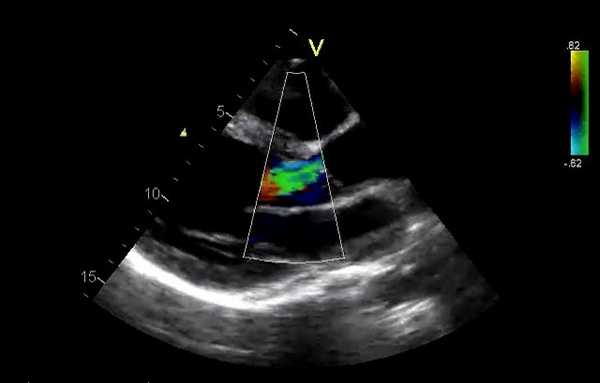

Допплеровская ЭхоКГ очень полезно для оценки функции протезного клапана:

Регургитация. Она может происходить через отверстие клапана (чрезклапанная) или вокруг пришивного кольца (парапротезная). Легкая транскалапанная митральная регургитация может быть обнаружена в нормально функционирующих клапанах, чаще в механических клапанах. Это связано с закрытием клапана или из-за зазоров между разными частями протеза. Ее бывает трудно обнаружить из-за маскировки тенью протеза. Умеренная или тяжелая митральная регургитация всегда считается патологической.

Непрерывно-волновой допплер более полезен, чем импульсный, а цветное допплеровское картирование кровотока (ЦДК) хорошо для отображения антероградных и ретроградных потоков. Турбулентный кровоток регистрируется в виде мозаики цветов. В митральных биопротезах обычно видна одна струя. В большинстве митральных механических клапанов видны 2 струи (почти равного размера у клапанов Старра - Эдвардса, одна меньше другой в клапанах Бьорка - Шайли).

При регургитации может быть несколько струй разного размера в зависимости от типа клапана (например, 2 струи у Бьорка - Шили, несколько у Старра - Эдвардса). ЦДК также помогает различать чресклапанную и парапротезную регургитацию и помогает выявить новую регургитацию.